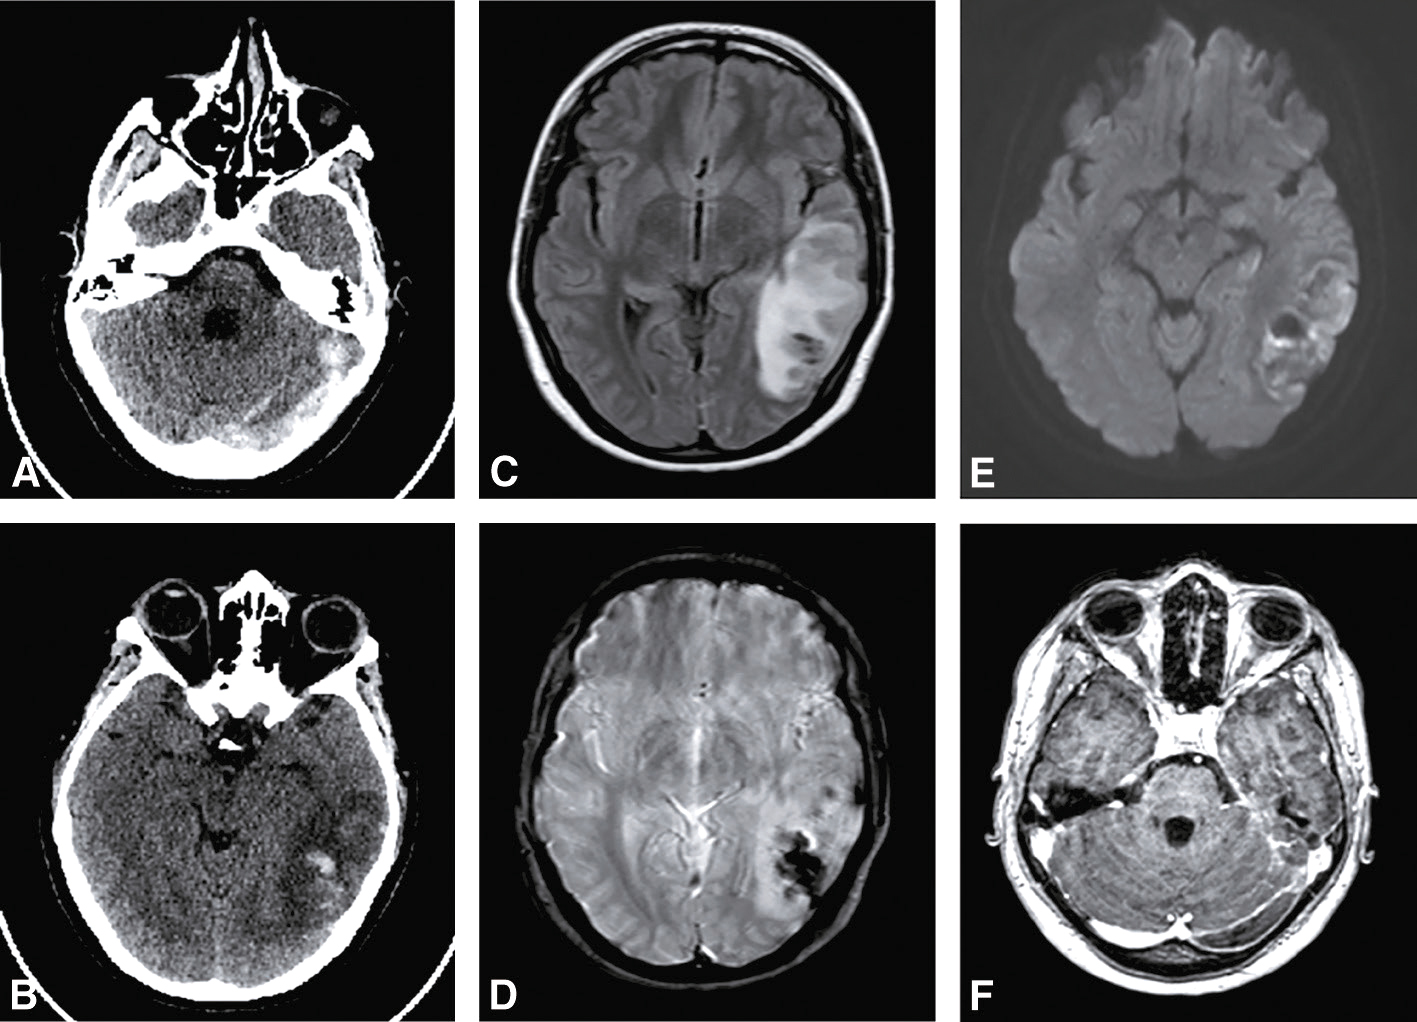

C Hémorragies intraparenchymateuses

• • On distingue les hémorragies intraparenchymateuses en fonction de leur localisation :

• – hématomes profonds (noyaux gris) (fig. 28.7A et B);

Fig. 28.7 Figure Hémorragies intracérébrales.

A. Hématome sous-cortical de l’HTA en scanner. B. Hématome sous-cortical de l’HTA en IRM (séquence T2*). C. Hématome lobaire de l’angiopathie amyloïde en scanner. D. Hématome lobaire de l’angiopathie amyloïde en IRM (séquence T2*).

• – hématomes superficiels (ou « lobaires ») (fig. 28.7C et D);

• – hématomes sous-tentoriels (tronc cérébral, cervelet).

B 527528Hémorragies intraparenchymateuses

1 Microangiopathie associée à l’HTA chronique

• FigureCause de 50 % des hémorragies intraparenchymateuses.

• • L’hémorragie intraparenchymateuse est secondaire à la rupture des artérioles perforantes, due à l’HTA chronique (fig. 28.7A et B).

• • L’hémorragie intraparenchymateuse associée à l’HTA est typiquement profonde.

2 Rupture d’une malformation vasculaire

• • Elle ne concerne qu’environ 5 à 10 % des hémorragies intraparenchymateuses, mais au moins un tiers chez le sujet jeune.

• Figure Il peut s’agir d’un(e) :

• – malformation artérioveineuse;

• – cavernome (malformation cryptique, c’est-à-dire non visible à l’angiographie) : il peut être isolé ou multiple (cavernomatose, le plus souvent génétiquement déterminée).

3 Trouble de l’hémostase

• FigureLe trouble peut être d’origine :

• – congénitale (hémophilie…);

• – acquise (anticoagulants, alcoolisme chronique…).

• Figure Parmi les causes acquises, l’origine iatrogène est prédominante.

• • Environ 10 % de l’ensemble des hémorragies intraparenchymateuses est lié à la prise d’anticoagulants oraux au long cours. Le risque des antiplaquettaires est beaucoup plus faible.

4 Tumeurs cérébrales

• • Cause de 5 à 10 % des hémorragies intraparenchymateuses.

• • Les tumeurs malignes sont les plus concernées.

• • L’hémorragie intraparenchymateuse est souvent révélatrice de la tumeur.

5 529Autres causes

Figure Elles sont nombreuses :

• • angiopathie amyloïde (hémorragies intraparenchymateuses lobaires récidivantes + déficit cognitif), cause fréquente chez le sujet âgé (fig. 28.7C et D);